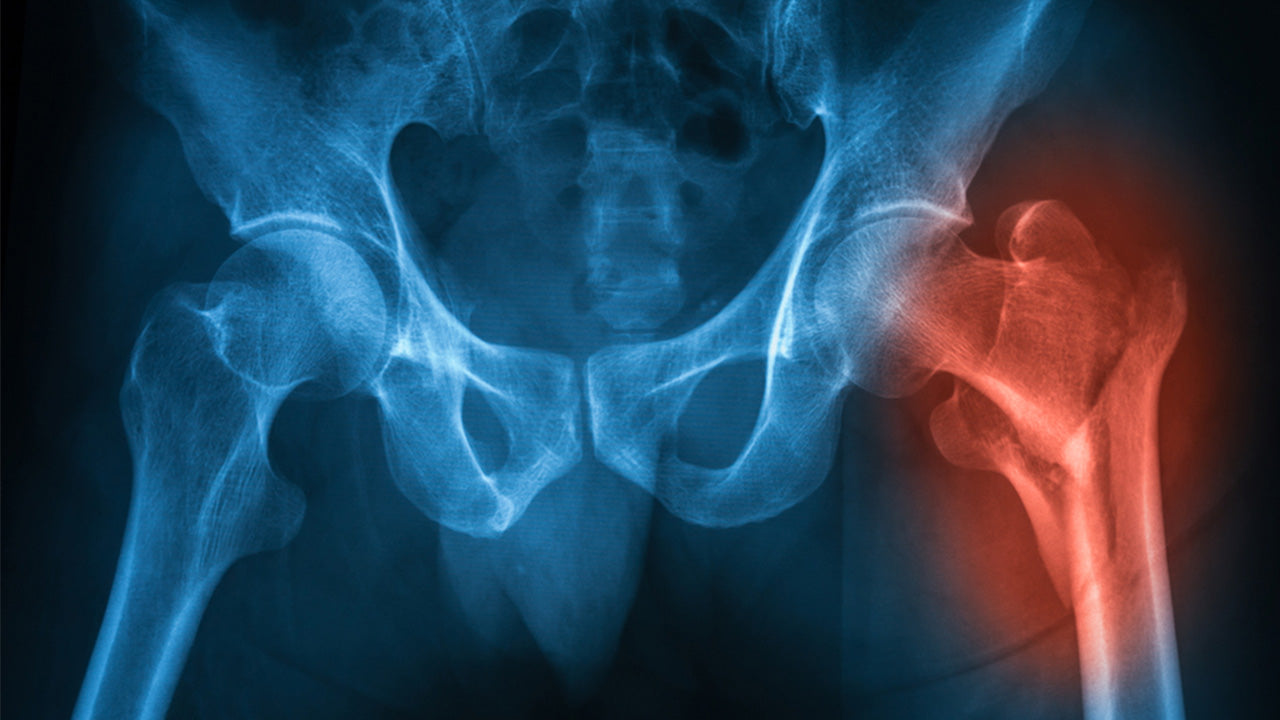

Most hip fractures occur as one of two types and can be identified with an X-ray.

- Femoral neck fracture: A break in the upper portion of the femur (1-2 inches from the ball and socket joint) that is commonly attributed to osteoporosis in older adults. This type of hip fracture can cut off blood supply to the top of the femur.

- Intertrochanteric fracture: A break further down the hip joint (3-4 inches) that does not impair blood supply and is often easier to correct.